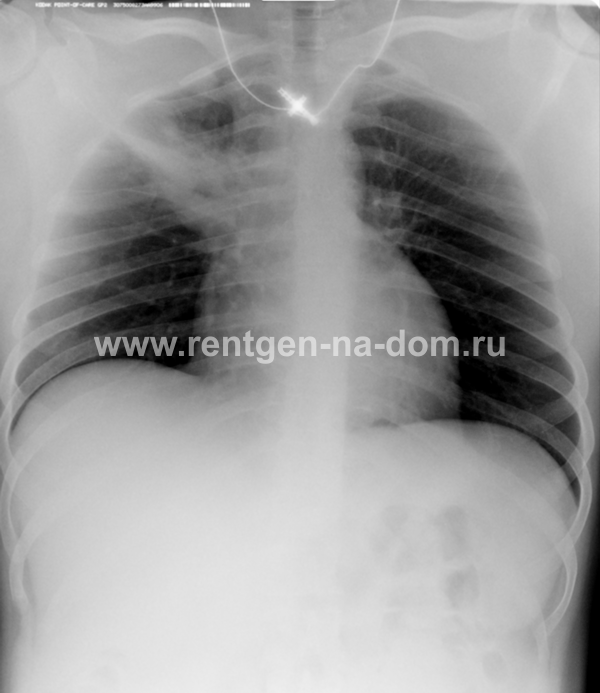

Пневмония – простыми словами воспаление легких – острое воспаление легочной ткани инфекционного происхождения с преимущественным поражением альвеол и интерстициальной ткани легкого. При этом жидкость скапливается в просвете альвеол, что ведет к уменьшению дыхательной поверхности легких. Пневмония может быть самостоятельным заболеванием или быть осложнением другого. Заподозрить пневмонию можно при аускультации (выслушивании) легких при дыхании. Поздняя диагностика и задержка с началом антибактериальной терапии ухудшают прогноз заболевания, возможен летальный исход. Поэтому при малейших подозрениях необходимо сделать рентген легких, особенно пожилым пациентам, а при подтверждении диагноза – поставить вопрос об экстренной госпитализации. Пневмония может лечиться и дома, но такое решение может принять только врач, основываясь на оценке состояния больного, рентгенологической картины легкого и анализов крови. Лечение пневмонии в большинстве случаев требует внутривенного введения антибиотиков, инфузионной терапии (капельниц) и других препаратов. Пациенты, обратившиеся в медицинский центр «Ваше Здоровье», смогут получить весь комплекс необходимых лечебно-диагностических мероприятий, в т.ч. рентген на дому.

Второй наиболее частой причиной, по которой выполняется рентген грудной клетки, является травма груди с подозрением на перелом рёбер. Может показаться, что ушиб грудной клетки является несерьезным основанием, чтобы обратиться к врачу и сделать рентген. Однако приглушая боль приёмом обезболивающих препаратов, можно пропустить ряд опасных осложнений. Сломанные рёбра могут ранить легкое и вызвать пневмоторакс, т.е. скопление воздуха, или гемопневмоторакс, т.е. скопление крови и воздуха в грудной полости. Перелом трех и более рёбер может вызвать серьёзные дыхательные нарушения, что особенно опасно у пожилых пациентов. Поэтому не стоит рисковать здоровьем и необходимо сразу обратиться к врачу. Пациенты, обратившиеся в наш медицинский центр "Ваше Здоровье", смогут получить весь комплекс необходимых лечебно-диагностических мероприятий, в т.ч. рентген на дому.

Получение качественных рентгеновских снимков на дому предъявляет серьёзные требования к рентгеновской аппаратуре. Далеко не каждый переносной рентгенаппарат позволяет получать снимки необходимого качества, чтобы достоверно поставить диагноз. Используемый нами рентгенаппарат АРА 110/160 в комплексе с компьютерным радиографом позволяет получать цифровые рентгеновские снимки высокого качества у пациентов различной комплекции и является уникальной услугой в Санкт-Петербурге, предоставляемой на дому.